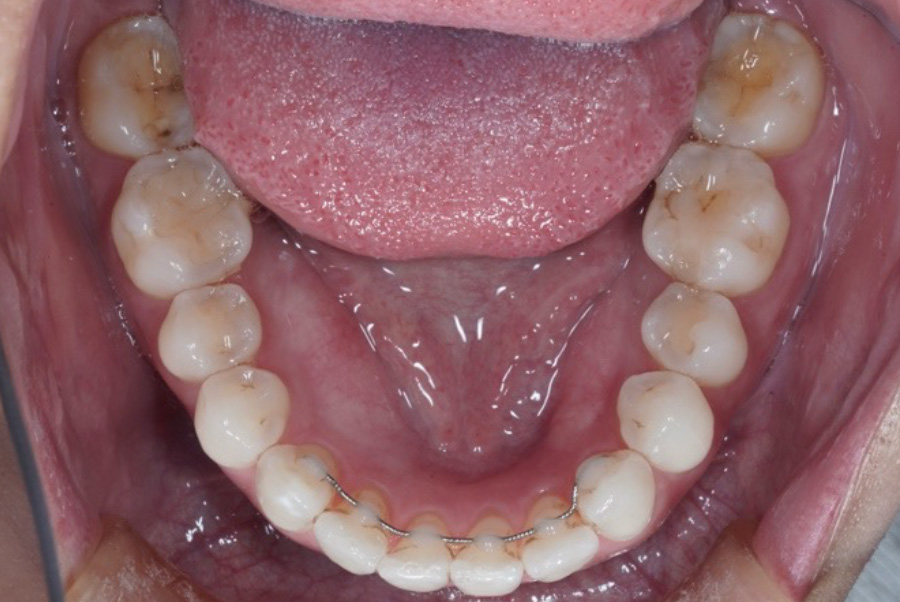

現在6年経過リテーナーの役割とは?

②固定式リテーナー

(フィックスリテーナー)

前歯の裏側に細いワイヤーを接着して固定するタイプ。外からは見えません。

常に装着されており、後戻りを強力に防止。装着忘れの心配なし。